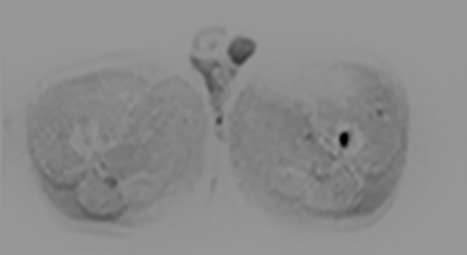

七、全身类PET成像,此项检查技术主要用于全身转移肿瘤的筛查:

①磁共振类 PET成像对全身恶性肿瘤病变性质的诊断,尤其对全身转移灶的筛查,淋巴结转移筛查及恶性肿瘤的分期评估具有很高的价值。②对已明确发现转移性病灶寻找其原发灶;术后放化疗的效应观察等具有较大优势。③对高危人群的肿瘤筛查具有实用价值。